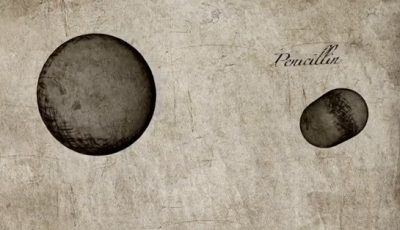

Discovery of penicillin | Pain, Pus and Poison: The Search for Modern Medicine

Discovery of penicillin | Pain, Pus and Poison: The Search for Modern Medicine

Fleming initially discovered the antibacterial properties of mould that would lead to the disc...